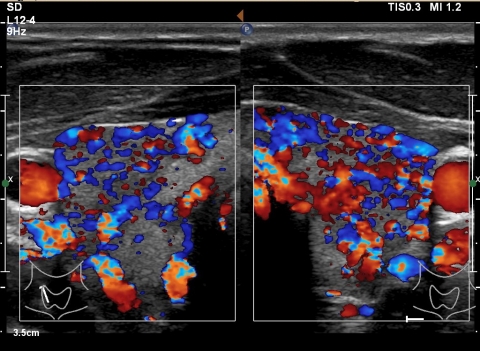

Praxis_Dr_Deiters_Hyperthyreose